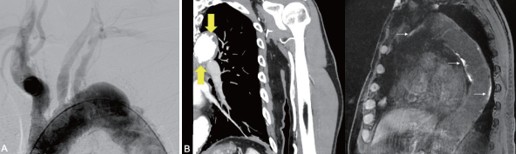

團裕之先生の論文、【Shaggy Aorta Syndrome after Cerebral Angiography: A Case Report】がJournal of NMS(2025;92(5):1409-413に掲載されました。 脳血管造影後に Shaggy aorta syndrome を発症した高齢患者の症例を報告しました。カテーテル操作や抗凝固療法によりコレステロール塞栓を生じ、脳梗塞および末梢塞栓症状を呈し、造影CTで shaggy aorta を診断し、発症後の大動脈MRIでは不安定プラークが確認されました。

重度動脈硬化を有する症例では、脳血管造影前の大動脈MRIスクリーニングの重要性が示唆されました。